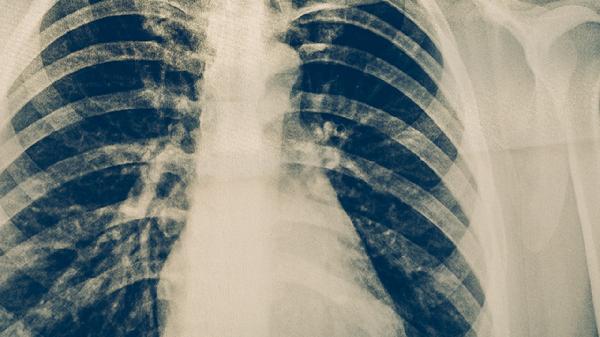

极少数情况下,医生可能根据痰菌转阴情况、影像学改善及药物不良反应调整方案,但必须由专科医生评估决定。对于出现严重药物过敏或肝功能损害的患者,需在医生监督下更换药物而非直接停药。治疗期间应定期复查痰涂片、胸部CT和肝功能,确保疗效与用药安全。